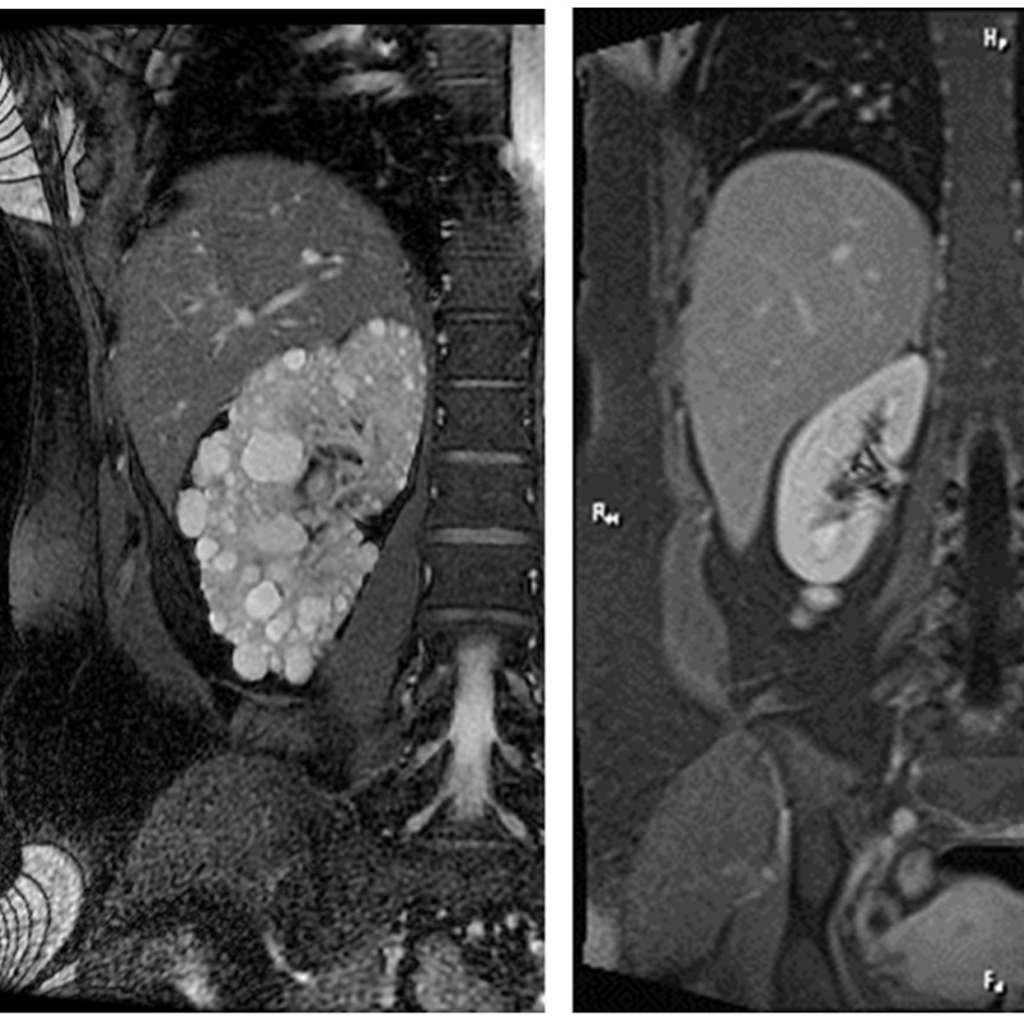

▲磁振造影下,左圖為多囊腎,右圖為正常腎臟。(圖片/新竹台大分院提供)

一名過去無特殊疾病史、身體也沒有任何症狀的35歲男子,最近因員工健康檢查發現有血尿情況,向新竹台大分院腎臟科門診做進一步檢查,發現兩側腎臟有許多大小不一的水泡,被診斷為「多囊腎」。多囊腎常見的原因是遺傳性腎臟病,醫師建議家屬也要檢查,並要定期追蹤。

腎臟內科醫師張勤斌說明,多囊腎稱為「自體顯性多囊性腎臟病」,是基因缺陷引起的。患者可能出生時腎臟就有囊腫,普遍在30~40歲後,出現症狀才被診斷出來。近年來健康檢查的觀念普遍,或因尿液檢查異常或超音波檢查而發現。病人腎臟功能會因年齡增長漸漸變差,可能惡化為末期腎病變,需要長期接受透析治療或接受腎臟移植。